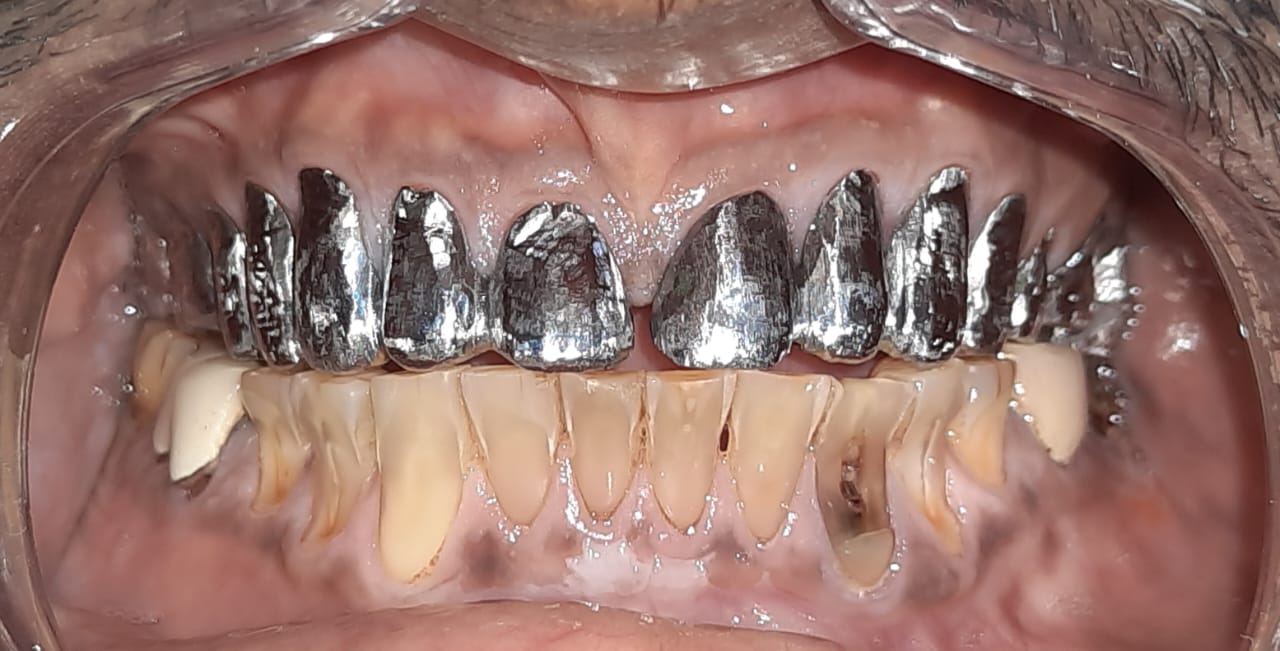

Patient wanted to get a new set of new teeth as old teeth were severely attrited and he was not able to chew. Medical history was taken and patient was fit for all the dental procedure. A detailed radiographic examination was conducted with the help of opg Treatment planning. A detailed case history along with radiological investigation and recording of of Bite of patient it was done in first visit. An appliance to relieve occlusion was given for 21 days Root canal treatment it was perform for all the teeth in subsequent visits. Occlusion was recorded using a specialised semi adjustable articulator. A temporary prosthesis was given to be used for or 15 days. A permanent Restoration was fabricated using pfm Crowns. A patience on patient end is a much needed thing as it involves time duration of of 1 to 2 months. Patient has to be absolutely serious about the treatment protocols which we are following as it involves use of appliances on patients end. Patient has to leave habit of eating Supari and tobacco as it was the cause in in severe reservation and attrition of teeth the artificial prosthesis is a finely crafted instrument that needs to be used with precision. so patients willingness and a positive mindset is Paramount in treating such cases.

Case Scenario 2 - Full Mouth Rehabitilation

Exciting News! Discover the Steps of Full Mouth Rehabilitation for a Dazzling Smile! Are parafunctional habits like kharra and ghutka taking a toll on your dentition? Say goodbye to improper chewing, loss of facial aesthetics, and digestive troubles with our expert team at Chintamani Dental Clinic!

Step 1: Accurate Diagnosis Using our in-house OPG, we pinpoint the issues to create a tailored plan just for you.

Step 2: State-of-the-Art Treatments Experience top-notch root canal treatments and effective temporization protocols for optimal oral health.